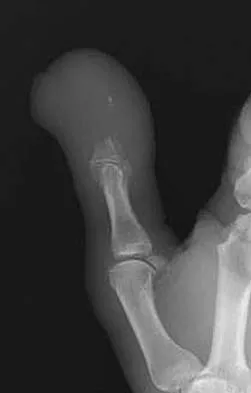

Figure 4a shows the radiograph of a 20-year-old man who has an injury to the right shoulder. Figure 4b shows an arthroscopic view (posterior portal). The arrow points to a

The radiograph shows an anterior dislocation of the shoulder. A frequently encountered sequela of this is a compression fracture of the posterolateral humeral head, commonly referred to as a Hill-Sachs defect. The arthroscopic view of the glenohumeral joint visualizes the posterior aspect of the humeral head. In the image, the area devoid of cartilage to the right is the bare area. The indentation seen to the left is a Hill-Sachs defect. Matsen FA, Thomas SC, Rockwood CA, et al: Glenohumeral instability, in Rockwood CA, Matsen FA (eds): The Shoulder, ed 2. Philadelphia, PA, WB Saunders, 1998, pp 611-754.

- Mazzocca AD, Noerdlinger M, Cole B, et al: Arthroscopy of the shoulder: Indications and general principals of techniques, in McGinty JB (ed): Operative Arthroscopy, ed 3. Philadelphia, PA, Lippincott Williams & Wilkins, 2003, pp 412-427.